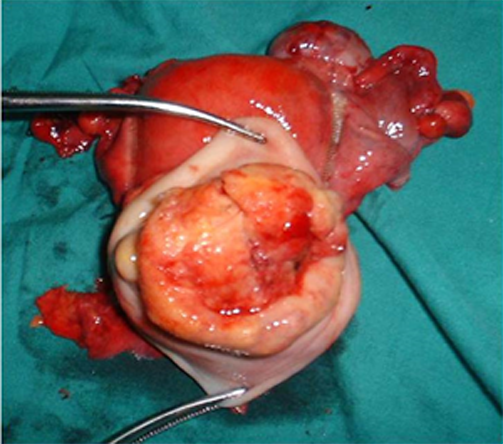

1.手术治疗 手术的优点是年轻患者可保留卵巢及阴道功能。主要用于早期子宫颈癌(ⅠA~ⅡA期)患者。①ⅠA1期:无淋巴脉管间隙浸润者行筋膜外全子宫切除术,有淋巴脉管间隙浸润者按ⅠA2期处理。②ⅠA2期:行改良广泛性子切除术及盆腔淋巴结切除术或考虑前哨淋巴结绘图活检(sentinel lymphnode mapping)。③ⅠB1期、和ⅠB2期ⅡA1期:行广泛性子宫切除术及盆腔淋巴结切除术或考虑前哨淋巴结绘图活检,必要时行腹主动脉旁淋巴取样。④部分ⅠB2期和ⅡA2期:行广泛性子宫切除术及盆腔淋巴结切除术和选择性腹主动脉旁淋巴结取样;或同期放、化疗后行全子宫切除术;也有采用新辅助化疗后行广泛性子宫切除术及盆腔淋巴结切除术和选择性腹主动脉旁淋巴结取样。未绝经、<45岁的鳞癌患者可保留卵巢。要求保留生育功能的年轻患者,ⅠA1期无淋巴脉管间隙浸润者可行子宫颈锥形切除术(至少3cm阴性切缘);ⅠA1期有淋巴脉管间隙浸润和ⅠA2期可行子宫颈锥形切除术加盆腔淋巴结切除术或考虑前哨淋巴结绘图活检,或和ⅠB1期处理相同;一般推荐ⅠB1期行广泛性子宫颈切除术及盆腔淋巴结切除术或考虑前哨淋巴结绘图活检,但若经腹或腹腔镜途径手术,手术指征也可扩展至ⅠB2期。

从左至右依次为Ⅰ、Ⅱ、Ⅲ及Ⅳ型子宫切除术的范围 Ⅰ型即筋膜外子宫切除术标本

Ⅲ型即广泛子宫切除术标本 盆腔淋巴结切除术标本